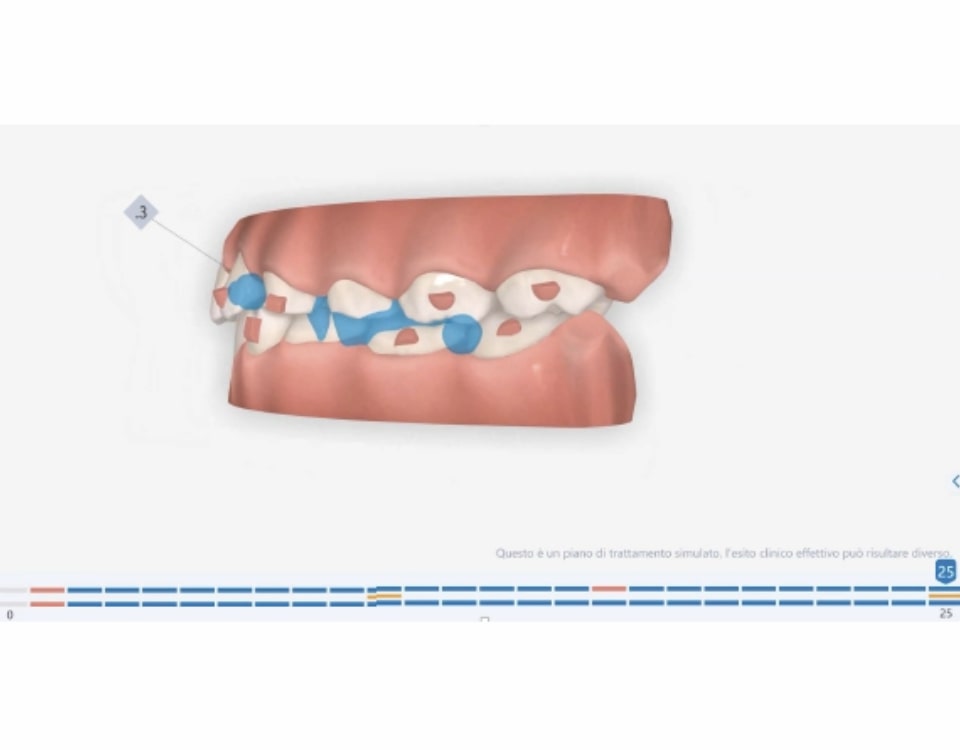

Number of aligners: 25

Malocclusion A6 Correction of Mandibular Retrusion in Growth phase patient | Skeletal Class II | Class II Division 1 malocclusion | Deep bite | Mixed dentition

Protocoles and features A6 Mandibular advancement

- Mandibular Advancement (A6 protocol) + angelBuon for Class 2 Elastics (Night Time)

Treatment setup

Treatment progress